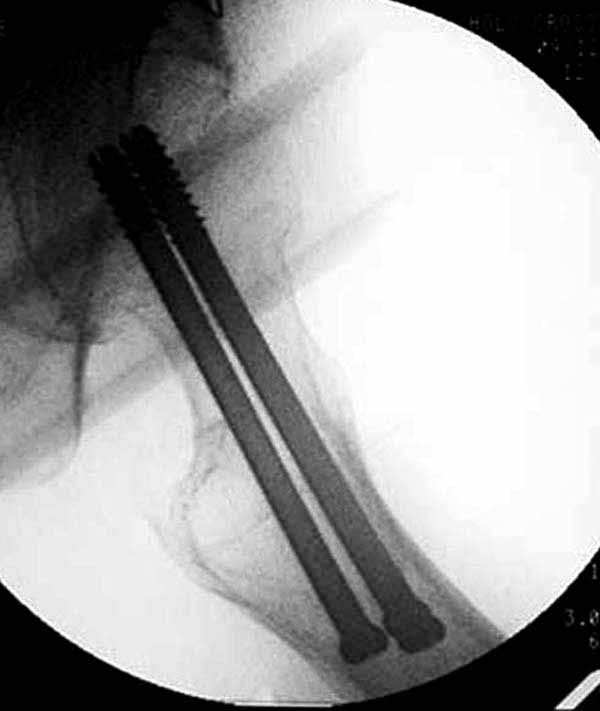

Здесь подобный случай, где стрессовый перелом обнаружен через 2 недели после фиксации. Применен Blade Plate с дополнительными шурупами.